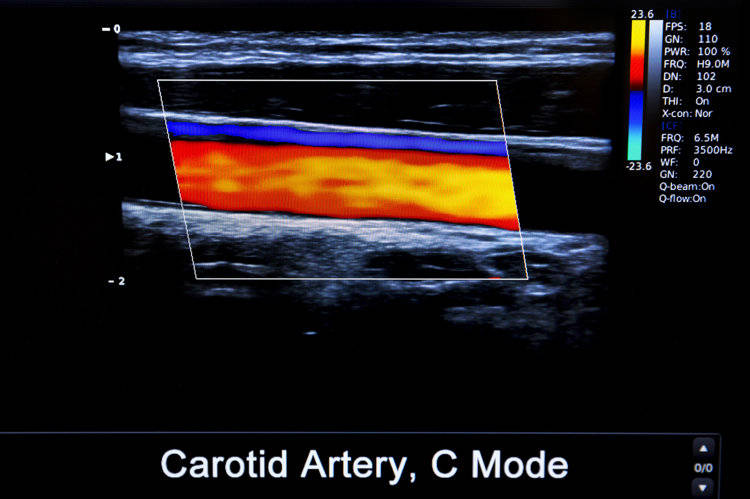

2、颈动脉斑块

动脉斑块是动脉内膜受损后脂类附着在受损处,最后由免疫细胞参与形成的。我国年龄>40岁的人群中有4成有颈动脉斑块,60岁以上的人群检出率高达90%。这就好比水管使用久了之后会产生水垢,是自然老化的表现。只要斑块性质稳定,没有造成血管明显狭窄,则无需过多处理。